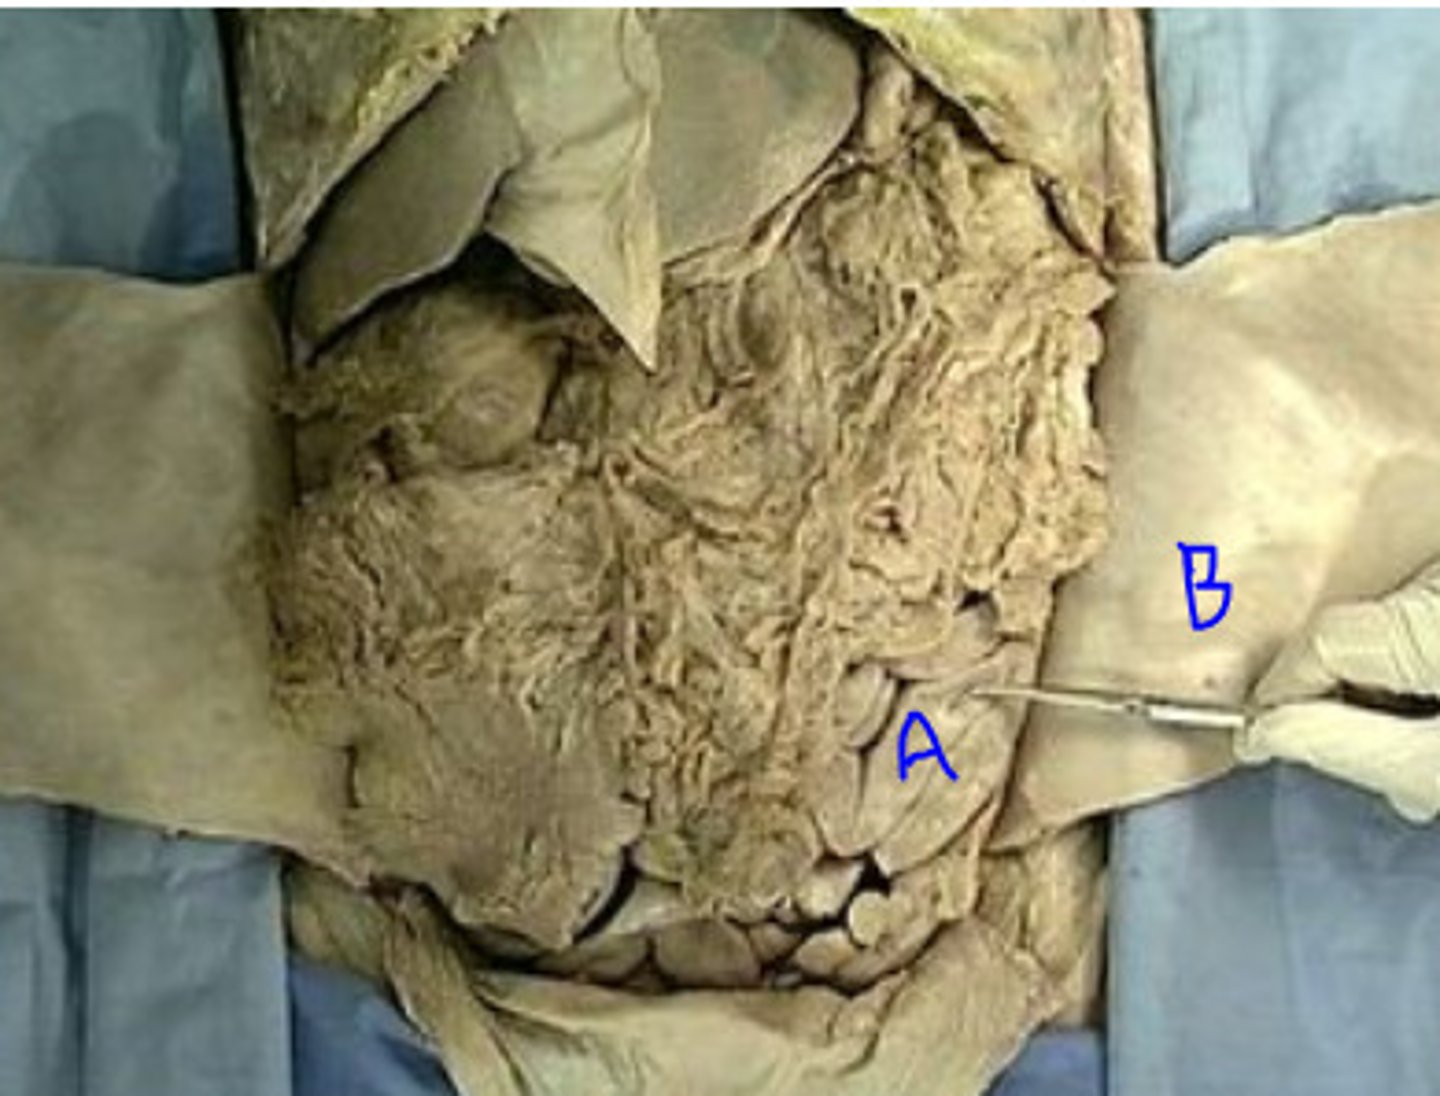

greater omentum

transverse mesocolon

mesentery proper

mesoappendix

peritoneal cavity

greater sac

jejunum

ileum

ileocecal junction

cecum

appendix